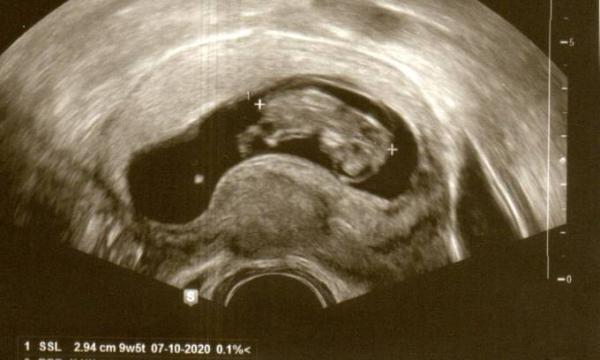

Hallo, ich bin 41 und das ist mein erstes Kind. Nach meiner Periode bin ich heute 11+2, mein Baby aber erst 10+0 Meine Fa hat beim 1. großen Ultraschall schon die Nackenfalte gemessen - da war das Baby erst 8+4 Ich weiß, dass es zu früh ist, eigentlich ja auch erst, wenn das Kleine 4,5 bis 8,5 cm erreicht hat und zwischen der 11. und 14. Woche. Bei der 1. Messung hatte sie eine Nackenfalte von 3,2 mm berechnet, 6 Tage später war ich nochmal dort und da waren es 4,4 mm Ich fragte sie, ob dies nicht zu früh sei, da meint sie, dass wenn es in dem Alter schon so ausgeprägt sei, kein gutes Zeichen ist. Morgen habe ich einen Termin beim Pränatalspezialisten. Ist zwar dann auch erst 10+1, aber, aber sie meinten, sie wollen sich schon mal selbst ein Bild machen, bevor ich jetzt nochmal 3-5 Wochen verrückt gemacht werde. Sie hätten viel bessere Geräte und könnten zumindest schon mal eine Tendenz nennen. Da ich eine Pessimistin bin, denke ich natürlich nach der Aussage der FA an das Schlimmste. Ich weiß man soll es nicht machen, aber natürlich google ich wie blöde und suche vergleichbare Bilder. Dabei bin ich dann auch zur Überlegung gekommen, ob es nicht noch das Amnion sein kann?! Ich weiß hier sind wir alle keine Ärzte, aber ich bin einfach so Ängstlich :(

Bild zu Nackenfaltenmessung zu früh und jetzt Panik - Schwanger mit 35 plus - Forum

Ja, da lag das kleine aber so in der Ecke, dass sie es nicht richtig messen konnte, da sieht man es am Kopf von oben und ich denke da ist es dann nicht das Amnion. In 2 Stunden geht es los, muss leider auch noch selber fahren - fahrt dauert ja 1 Stunde. Bin so nervös

Bild zu

Ich denk ganz fest an dich!!! Unser Termin ist um 13.00 Uhr. Hoffentlich ist es dir recht, wenn ich jetzt nicht auf das Bild eingehe, in ein paar Stunden hast du schon Gewissheit! Ich drück dir alle Daumen, dass du heute verlässliche Angaben bekommst! Und denk dran, es gibt vieles, was man auch schon in der Frühschwangerschaft untersuchen kann, neben Ultraschall. NIPT ist schon möglich, eine Chorionzottenbiopsie auch bald. Du wirst nicht ewig warten müssen, bis du mehr weißt! Und das schaffen wir! Fühl dich gedrückt, ich melde mich später!